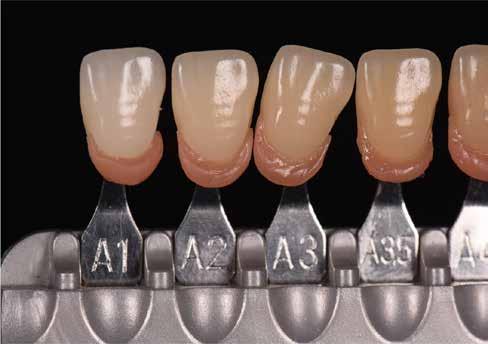

A színtudomány hatalmas komplexitásában magában foglalja többek között a fizikát, a matematikát, a geometriát, a mérést, az érzékelést, a kémiát, az optikát, a művészetet és az emberi pszichológiát. Dióhéjban a színtudomány a pszichofizika. A fogászati szakirodalomban gyakran találkozhatunk félreértelmezett színtudományi fogalmakkal és azok helytelen alkalmazásával. A fogászati területre vonatkozó összetett színtudományi fogalmakat gyakran nehéz könnyen érthető szavakkal elmagyarázni. A következő oldalakon megpróbálunk néhány ilyen fogalmat könnyebben érthető nyelvre lefordítani.